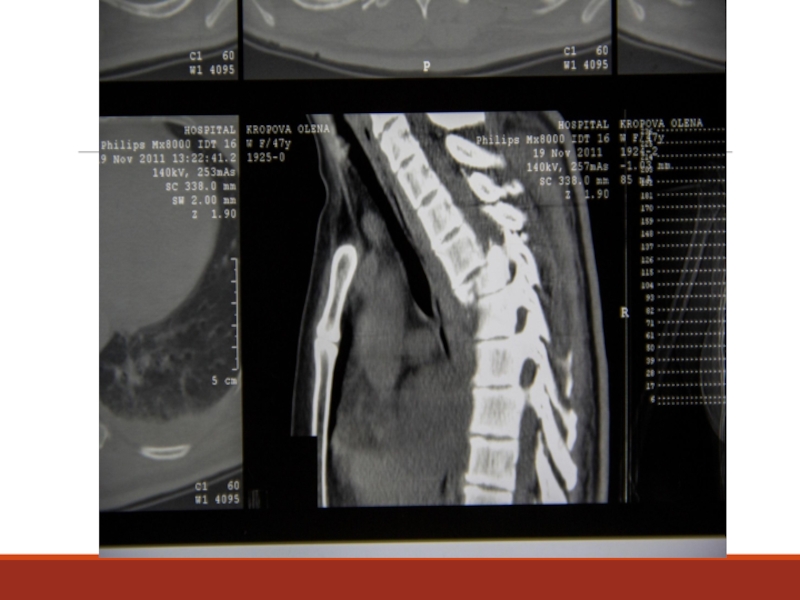

Слайд 51Абсолютные показания к операции при пояснично-крестцовой радикулопатии

1. Сдавление корешков конского хвоста

с парезом стоп

2. Анестезия аногенитальной области

3. Нарушение функции тазовых органов

4. Нарастание пареза в миотоме пораженного корешка

Слайд 52Относительные показания при шейной и поясничной радикулопатии

Выраженный корешковый (невропатический) болевой

синдром не поддающийся адекватному лечению в течение 6 нед., а также нарастание неврологических нарушений.

Слайд 53Причины послеоперационного люмбоишиалгического синдрома

1– это те кому изначально не было показано

оперативное лечение: фасеточный синдром, дисфункция КПС, психические расстройства

2– неправильно определенный уровень оперативного вмешательства, неполное удаление фрагментов грыжи, последствия самой операции.